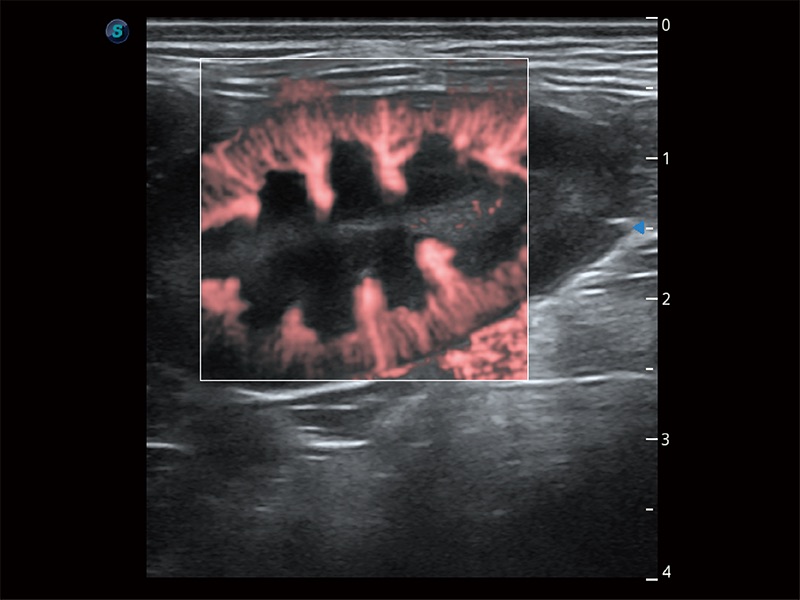

極大提升超低速微細(xì)血流的檢出能力,同時(shí)更精準(zhǔn)地濾除軟組織和超聲信號(hào),為獸用醫(yī)生提供以往無(wú)法通過(guò)常規(guī)血流獲得的疾病診斷信息。

在傳統(tǒng)二維血流成像的基礎(chǔ)上,呈現(xiàn)血流的立體感,具有動(dòng)感的生命力之美。即便是微小的血管也能輕松應(yīng)對(duì),提高了血流的視覺(jué)敏感性。